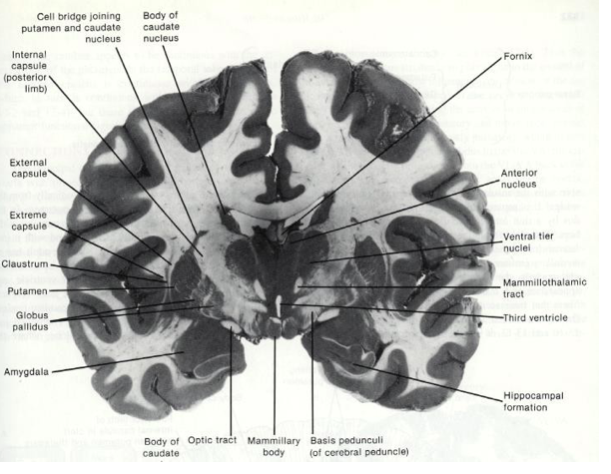

Fill in the blanks.

Fill in the blank.

Fill in the blank

Fill in the blanks